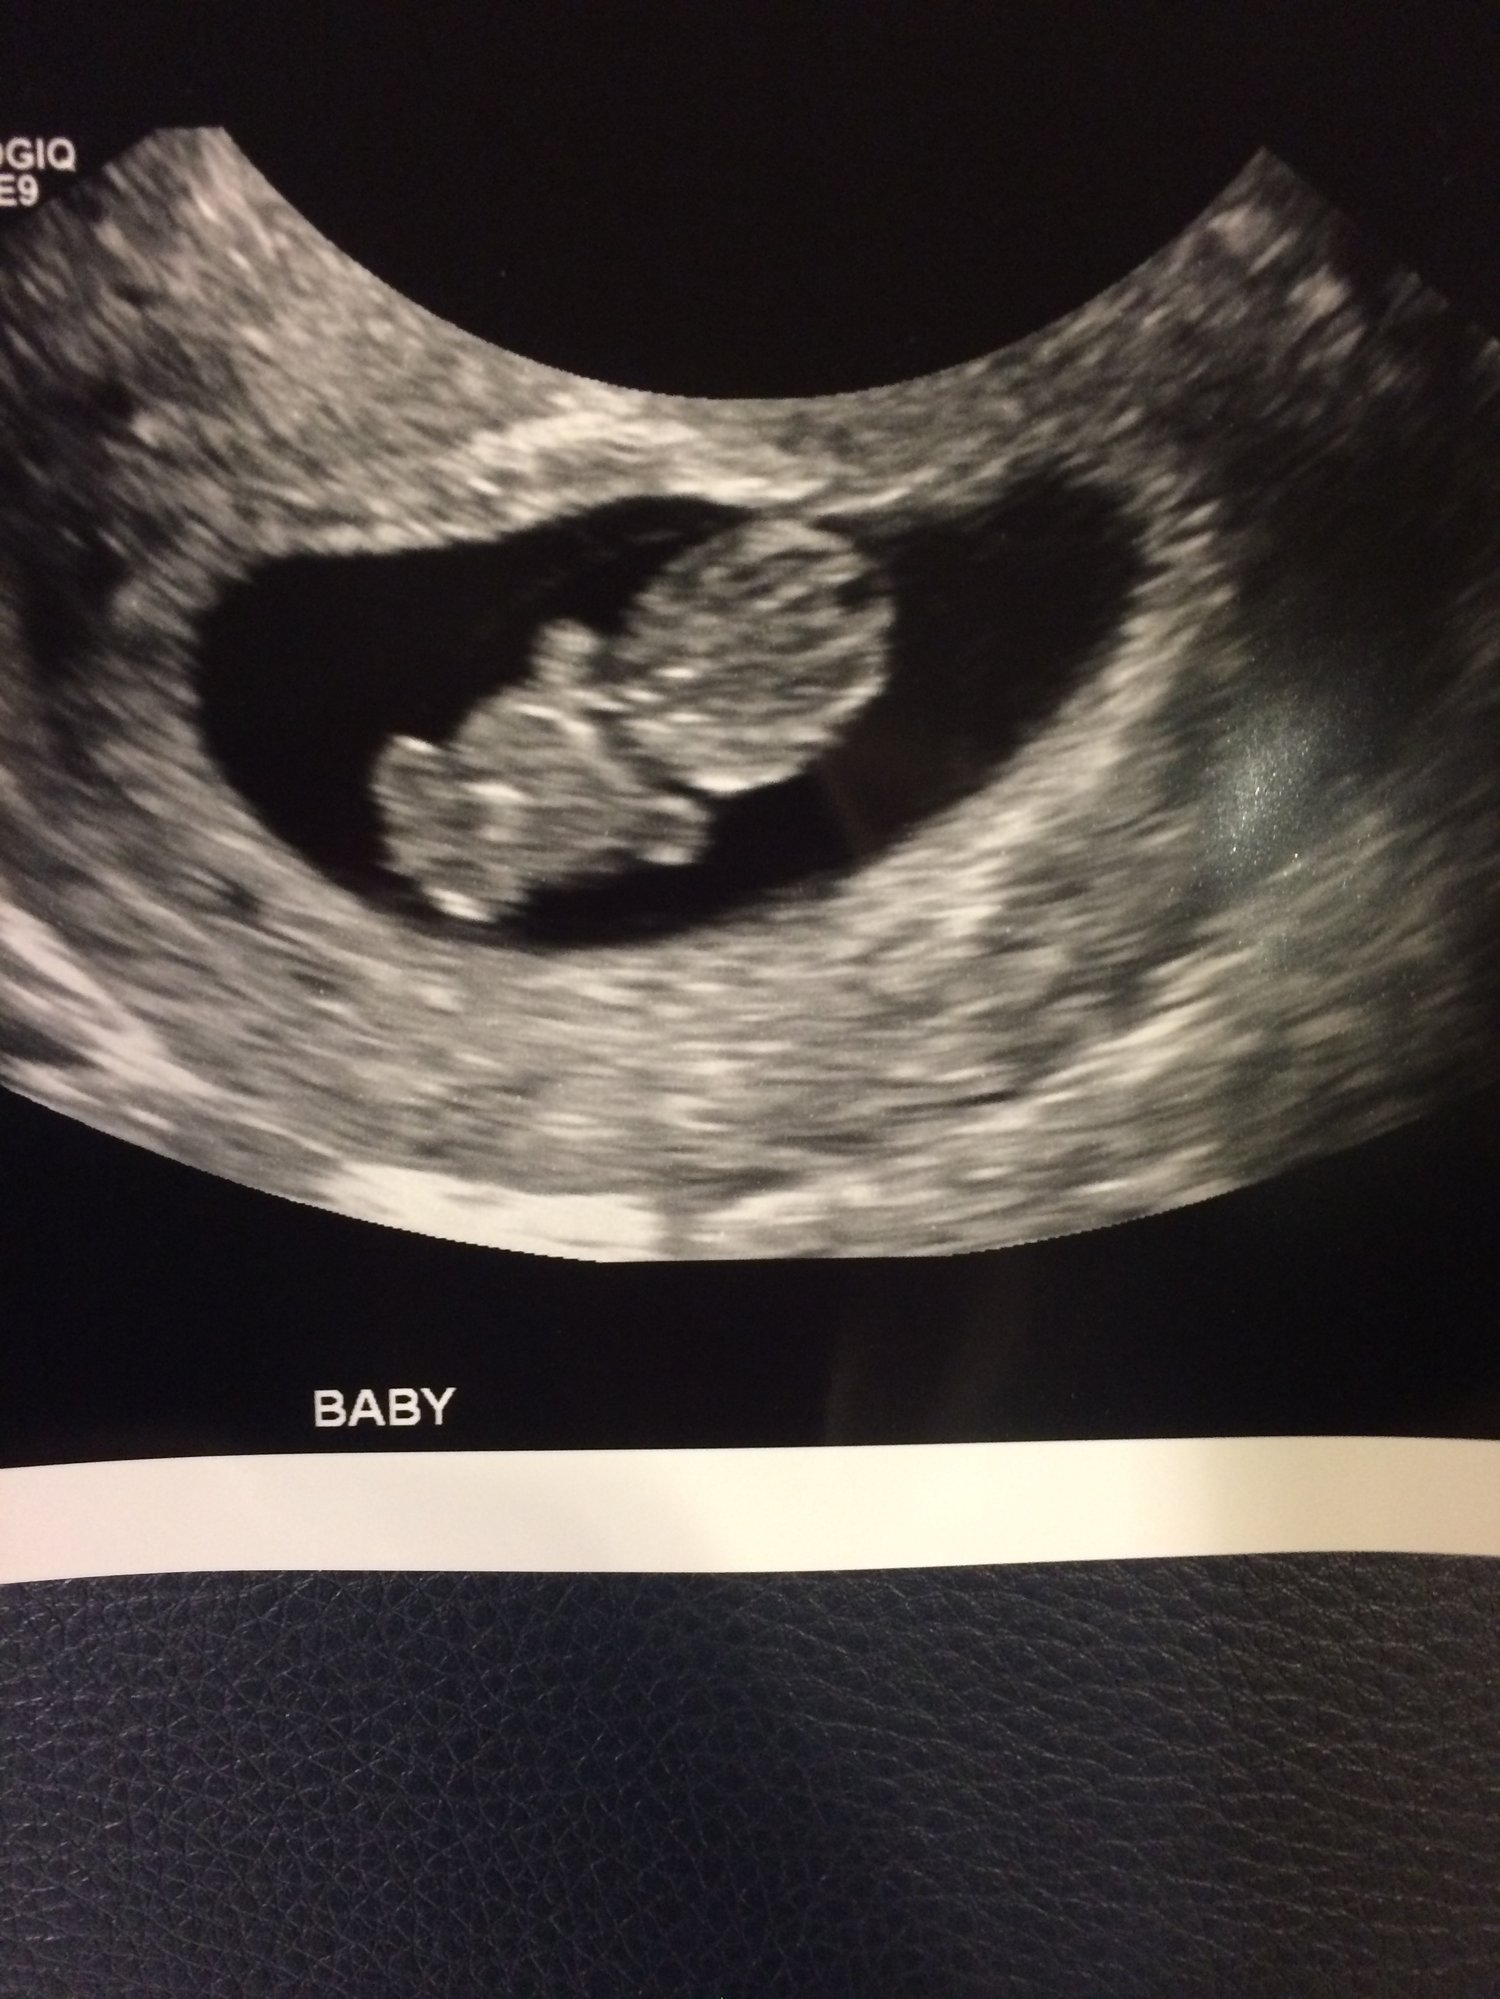

1. How far along are you?10 weeks

What is your EDD? June 8

I had one today! got to see the little babe with his cute legs and arms, and a fast beating heart